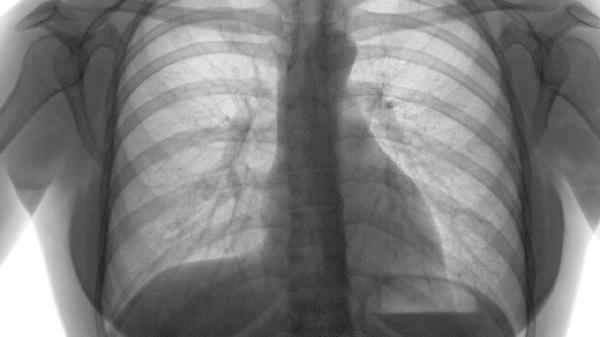

如何控制慢性阻塞性肺气肿

慢性阻塞性肺气肿可通过戒烟、药物治疗、氧疗、肺康复训练、接种疫苗等方式控制。慢性阻塞性肺气肿通常由长期吸烟、空气污染、遗传因素、职业粉尘接触、反复呼吸道感染等原因引起。

慢性阻塞性肺气肿患者需注意保暖防寒,避免接触冷空气和呼吸道刺激物。保持居住环境通风良好但避免直接吹风。饮食宜清淡易消化,适量增加优质蛋白摄入。根据自身情况选择适宜运动,以不引起明显气促为度。定期复查肺功能,出现咳痰增多、呼吸困难加重等情况及时就医。家属应学习基本护理知识,帮助患者建立健康生活方式。